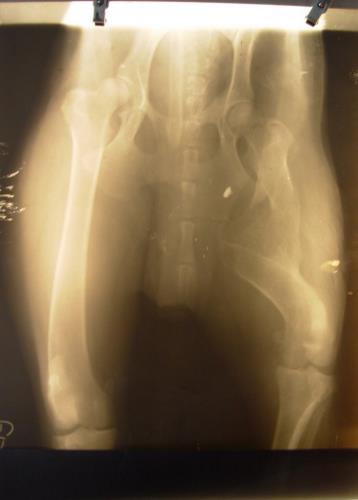

Çoban Kopeği in Turkey with Bullet in Leg

Dog with Bullet in Leg Dog with Bullet in Leg